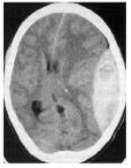

Paciente com história de TCE realizou a tomografia apresentada abaixo. Qual o diagnóstico do paciente?

Enunciado 859426-1